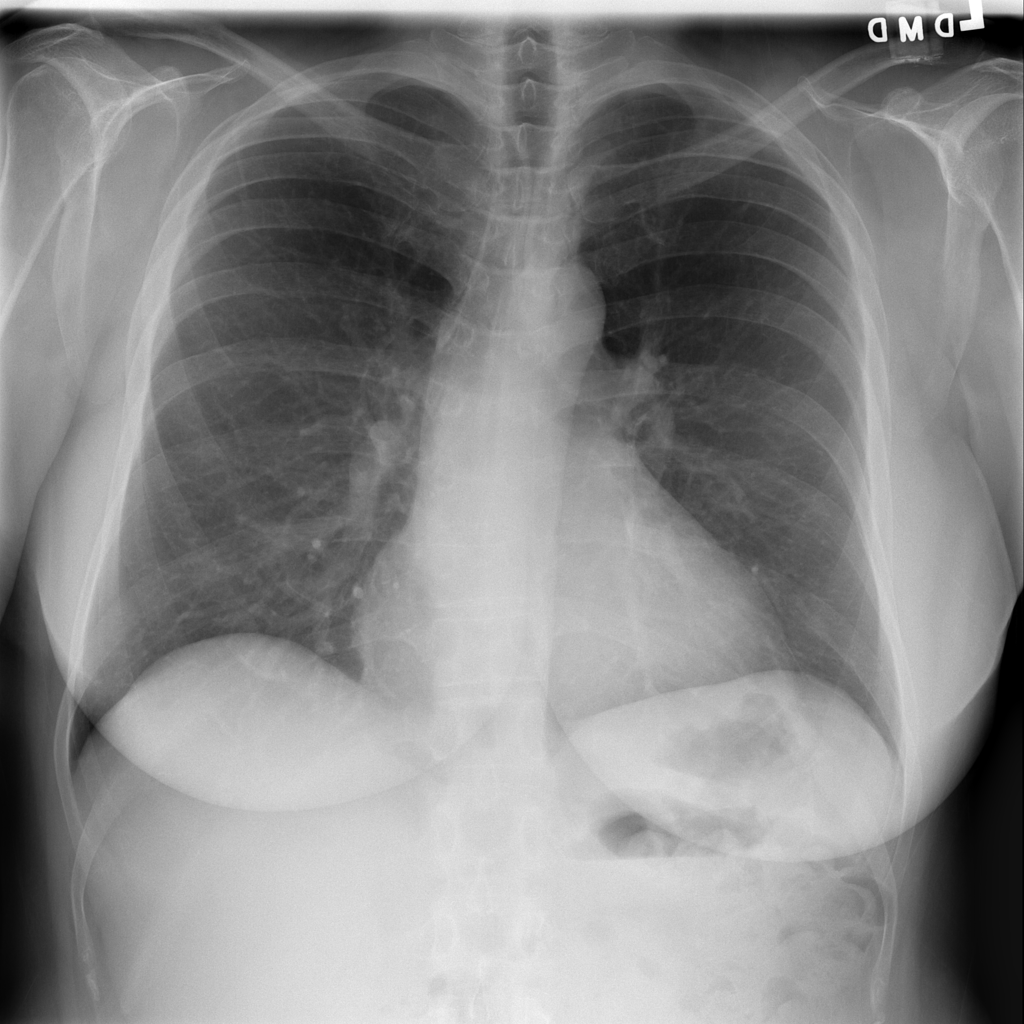

Nodule

A nodule is a small rounded opacity in the lung or chest field. It is a descriptive imaging finding that can be benign or more concerning depending on size, appearance, and context.

Showing up to 90 reference images for Nodule.

PAT-50E5 · IMG-000Nodule

PAT-50E5 · IMG-000

PA